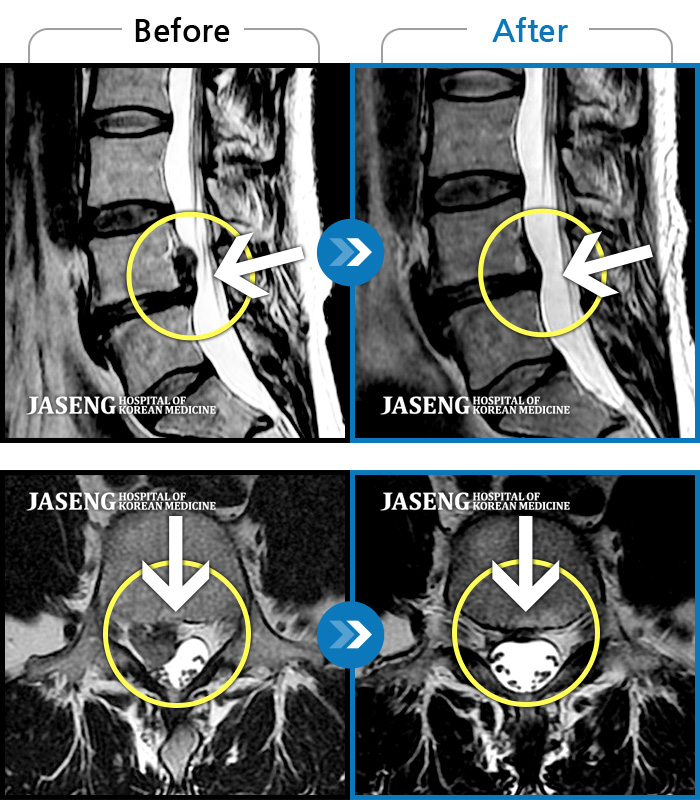

오른쪽 정강이 감각이 무디고, 발바닥 통증

2019.07.16 ~ 2020.02.13